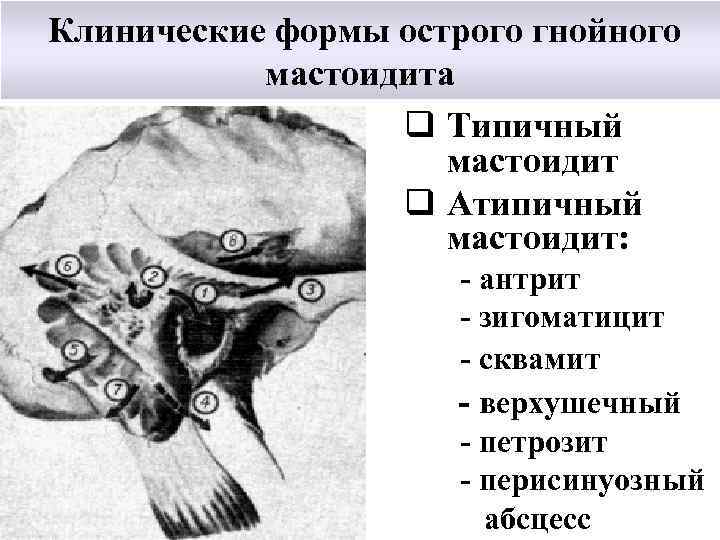

Клинические формы острого гнойного мастоидита q Типичный мастоидит q Атипичный мастоидит: - антрит - зигоматицит - сквамит - верхушечный - петрозит - перисинуозный абсцесс